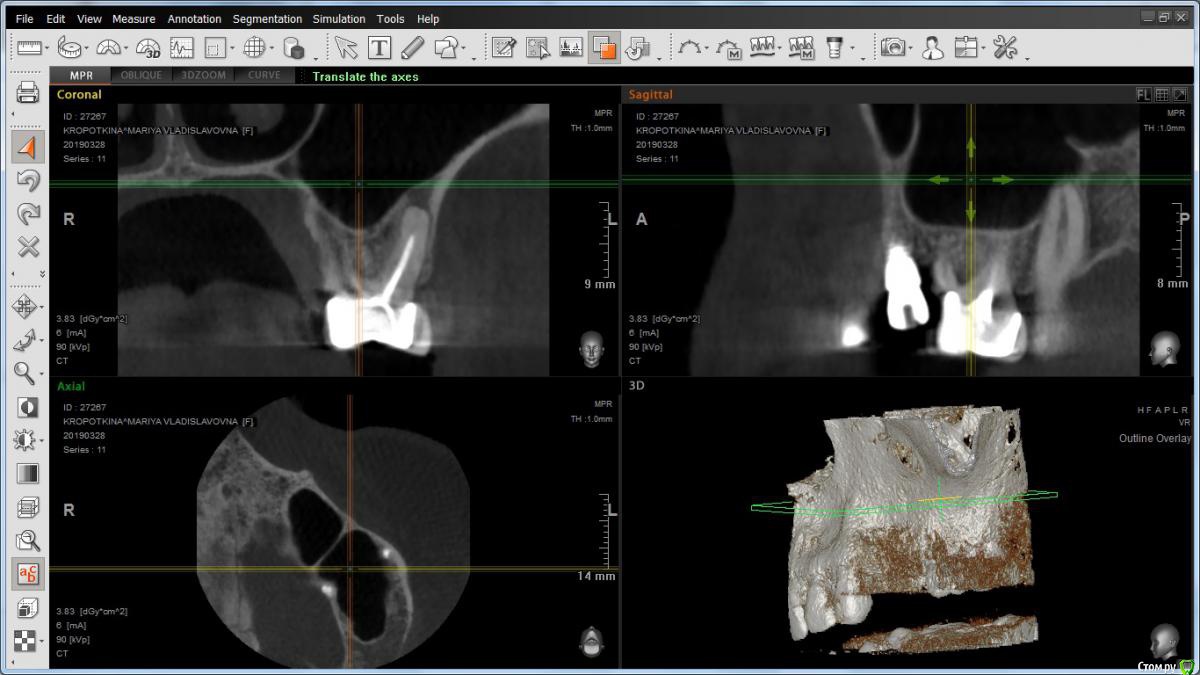

Marriyashka Опубликовано 29 марта, 2019 Поделиться Опубликовано 29 марта, 2019 (изменено) Добрый день! В июле 2018 года была установлена коронка (6) и 2 импланта (4, 5). Теперь при установке формирователей врач-имплантолог настаивает на удалении коронки и 5 импланта, и переустановке его на место 6, с последующим мостом. Действительно ли резорбция настолько серьезна? Заранее спасибо! Изменено 29 марта, 2019 пользователем Marriyashka Ссылка на комментарий

Marriyashka Опубликовано 31 марта, 2019 Автор Поделиться Опубликовано 31 марта, 2019 Врач говорит, коронка поставлена фигово, десна прилегает неплотно, под неё попадает пища, уже началась резорбция. Ссылка на комментарий